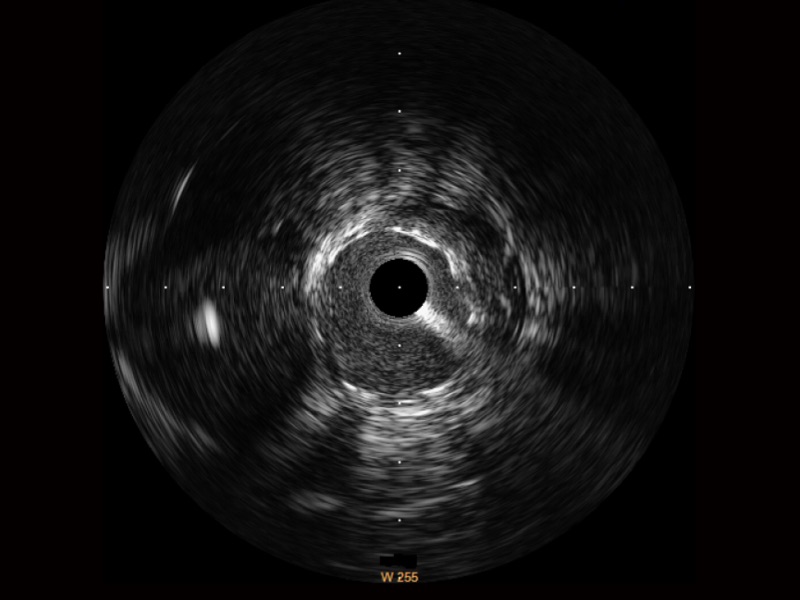

传统IVUS图像

对比传统IVUS导管成像,开立宽频IVUS图像的近场支架梁显影更细腻,远场中膜外血管仍清晰可辨,兼顾远中近,兼顾分辨力与穿透深度